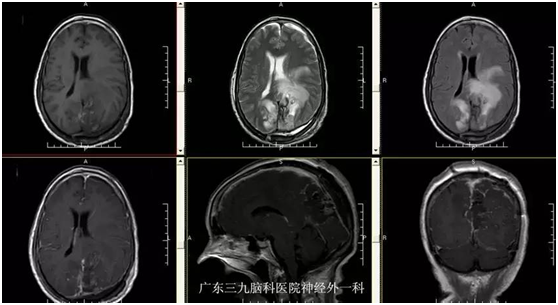

黄奶奶,72岁,因“视物模糊3个月,右侧肢体乏力半个月”入院。3个月前老奶奶无明显诱因下,出现左眼视物模糊,近半个月来出现右侧肢体乏力伴行走不稳,当地医院颅脑MR检查示:左侧枕叶镰窦旁占位性病变,门诊拟“左侧枕叶镰窦旁脑膜瘤”收入我院。入院视力1米数指。入院后完善相关检查,在全麻下行左侧枕叶镰窦旁脑膜瘤切除,手术后恢复良好,老奶奶视物较前改善,能下地行走。

视野缺损。甚至失明:脑膜瘤位于大脑后部时,可以引起视野改变,常未引起病人注意。检查可发现视野缺损。肿瘤常长到巨大体积时,巨大镰旁脑膜瘤可压迫双侧枕叶距状裂,造成失明。本例患者肿瘤正好压迫皮质视感觉区,出现视力严重下降。